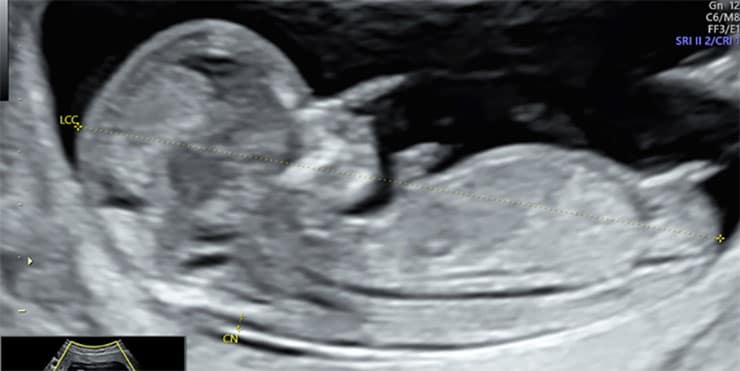

2. L’échographie du 1er trimestre (12 à 13 SA – 2 mois1/2)

Cette échographie, aussi appelée échographie de dépistage du 1er trimestre, est un examen complet du fœtus et du début de la grossesse.

Elle permet :

• De vérifier la vitalité du fœtus

• De contrôler la croissance et la morphologie précoce

• De mesurer la clarté nucale, un paramètre utilisé dans le dépistage de la trisomie 21

• De dater la grossesse avec précision si ce n’était pas encore fait

• D’observer le placenta, le cordon et les annexes

C’est un moment riche en émotions : votre bébé bouge déjà beaucoup et prend peu à peu une apparence humaine.